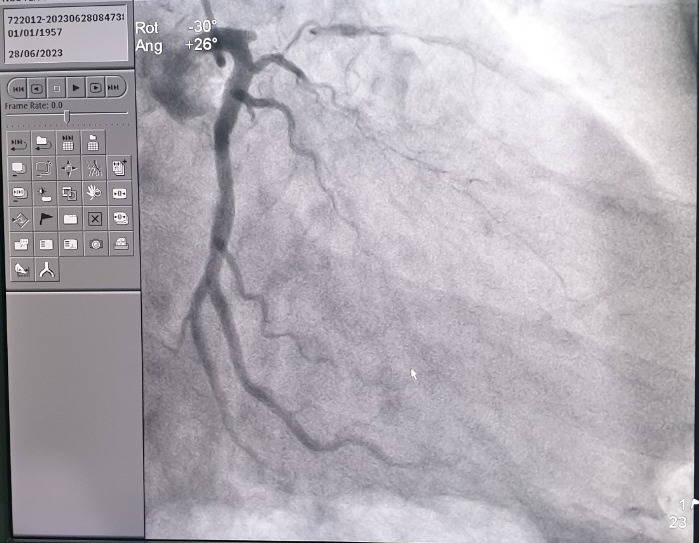

Nam bệnh nhân phát hiện động mạch vành bị hẹp khí mãn tĩnh, nguyên nhân chính là do thói quen hút thuốc lâu năm.